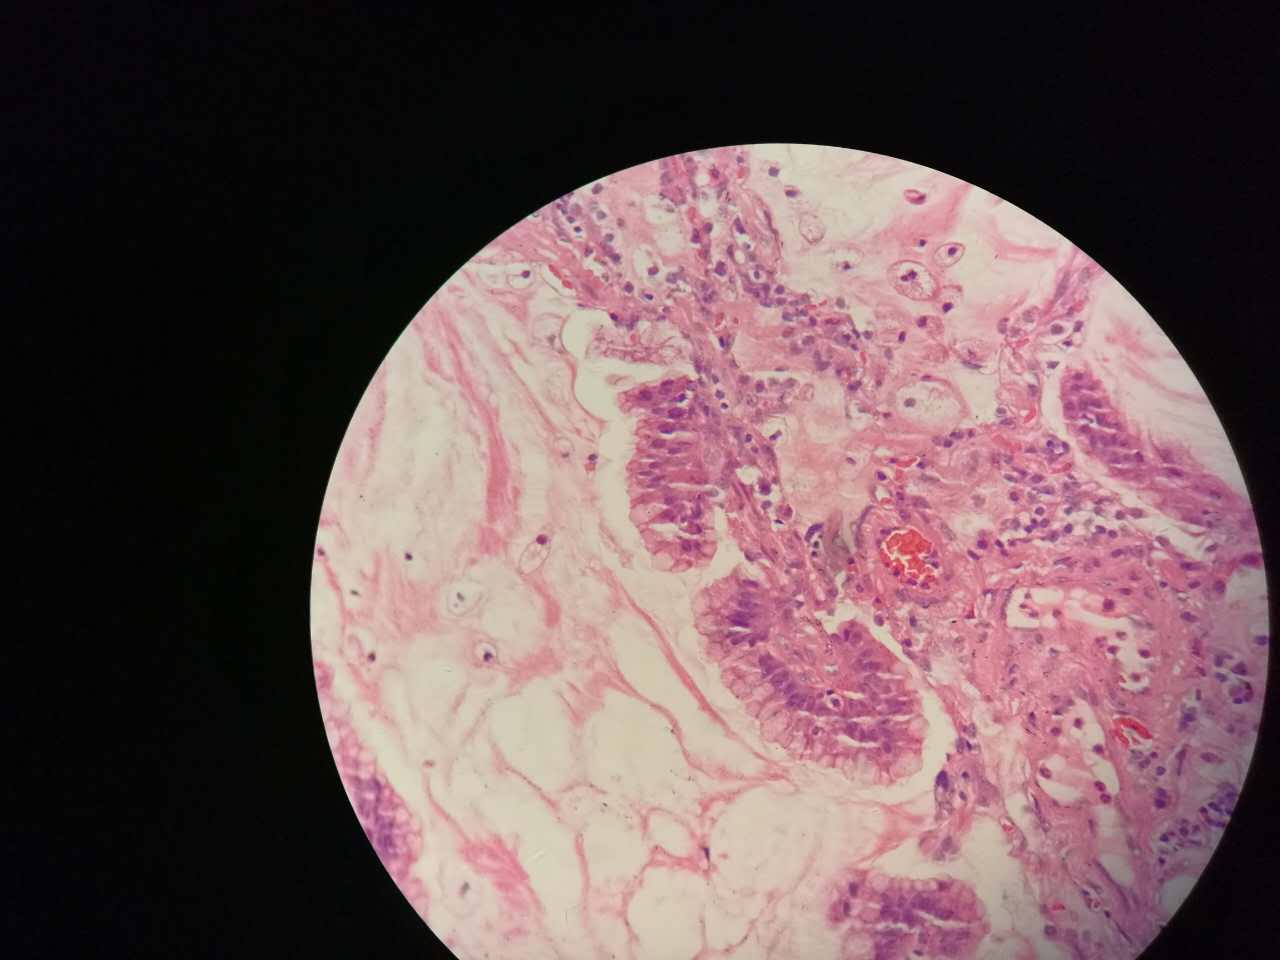

粘液型腺癌

粘液型腺癌是原发肺腺癌中的一种特殊类型

细胞内外含较多粘液

粘液型腺癌,细胞内粘液多,有点儿像支气管的粘液腺

单纯的粘液腺,没有浆液腺

细胞外粘液湖

粘液腺癌起源于细支气管和肺泡

粘液型腺癌的肿瘤细胞排列整齐,核位于基底,细胞呈柱状。

肺泡间隔(间质)经常比较细